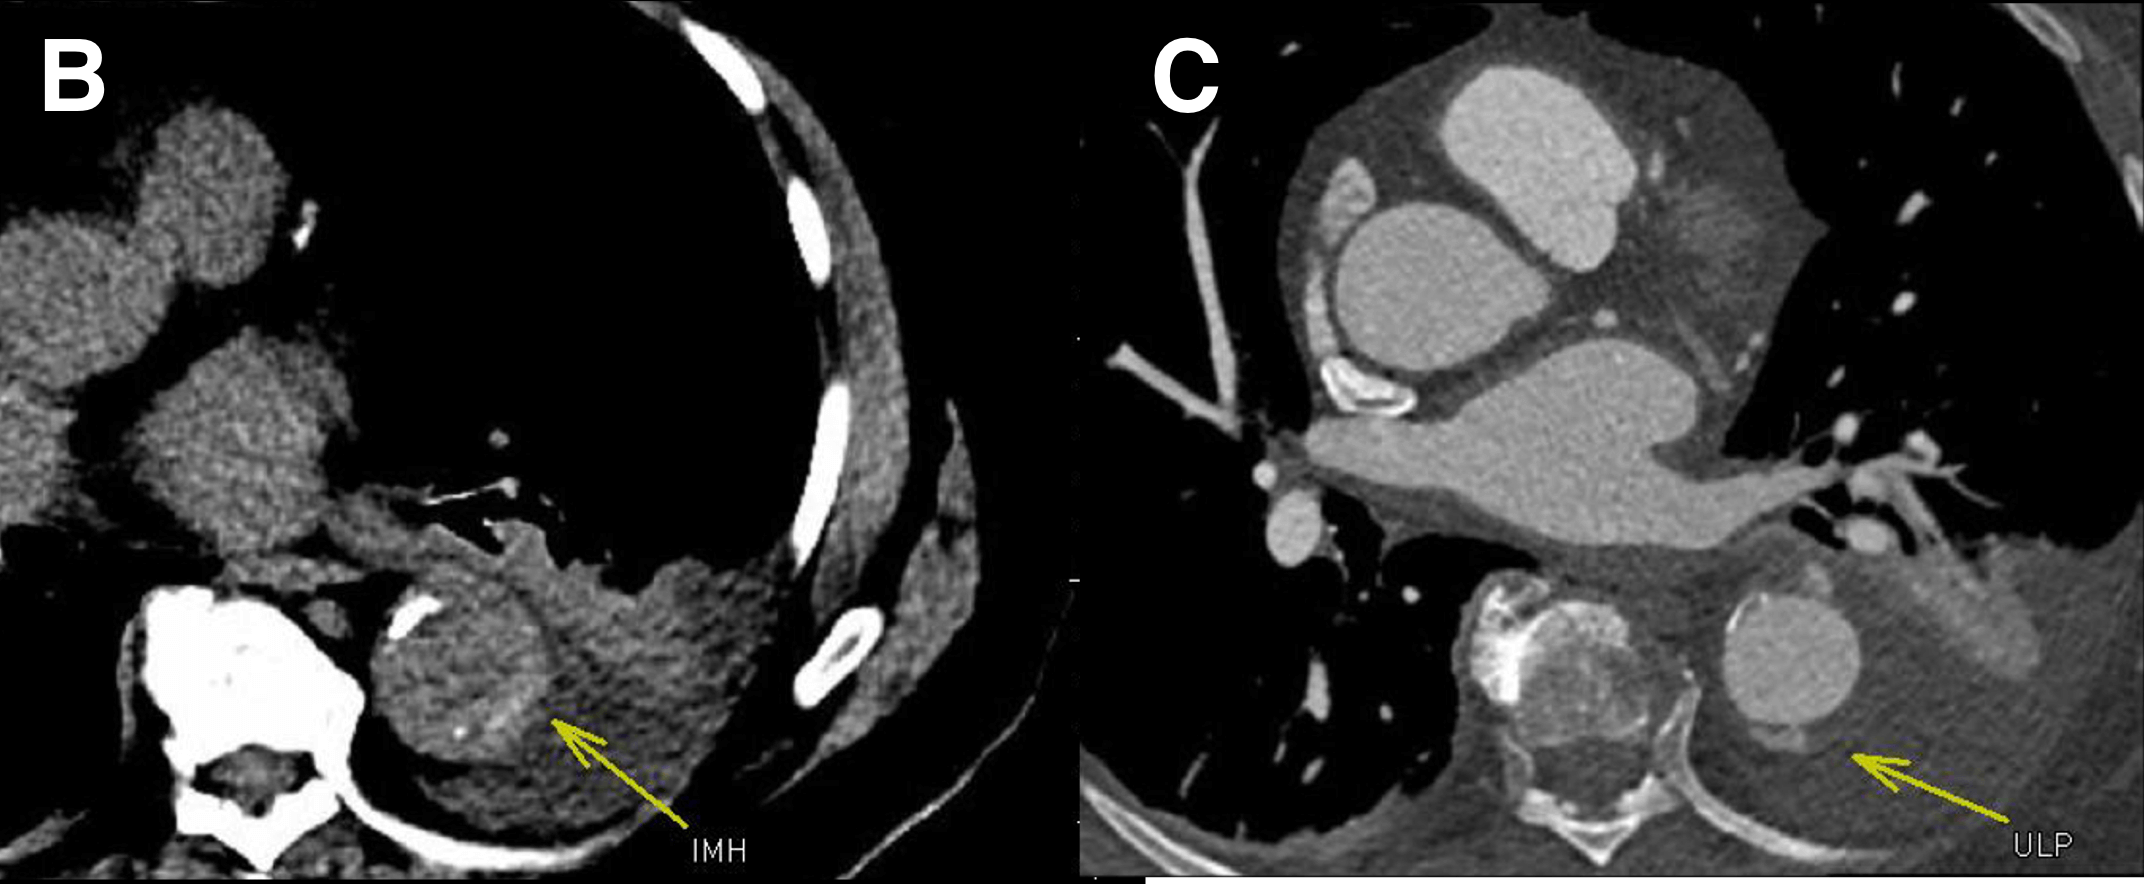

Figure B. Non-contrast series shows high density within the wall of the aorta, consistent with intramural hematoma (IMH, arrow).

Figure C. CTA images shows an adjacent ulcer-like projection (arrow, ULP).

IMH occurs from penetrating atherosclerotic ulcer (PAU) that extends across the internal elastic lamina into the media and/or adventitia. Ruprture of the vaso vasorum occurs, and blood collects in the aortic wall = IMH (arrow in B) . Extension though the adventitial structures can result in pseudoaneurysm or rupture (arrow in C).